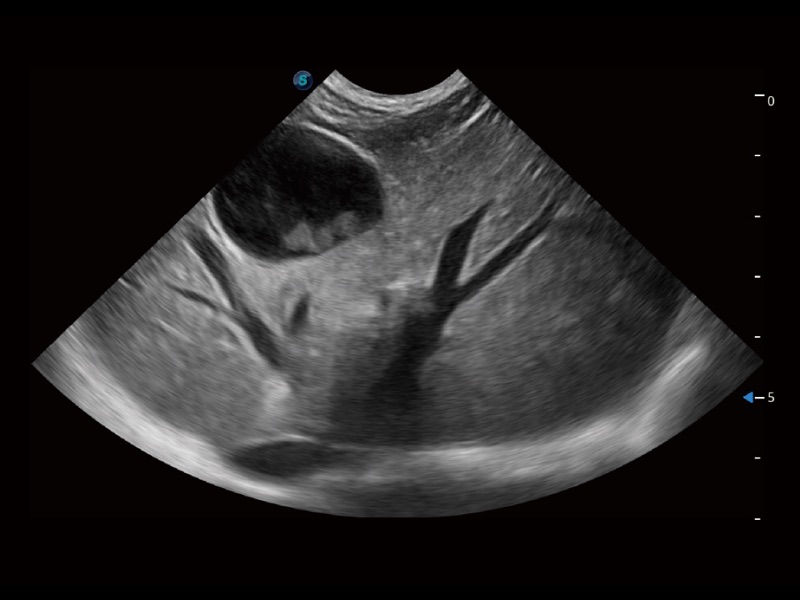

(猫)胆囊

(猫)肺动脉血流频谱